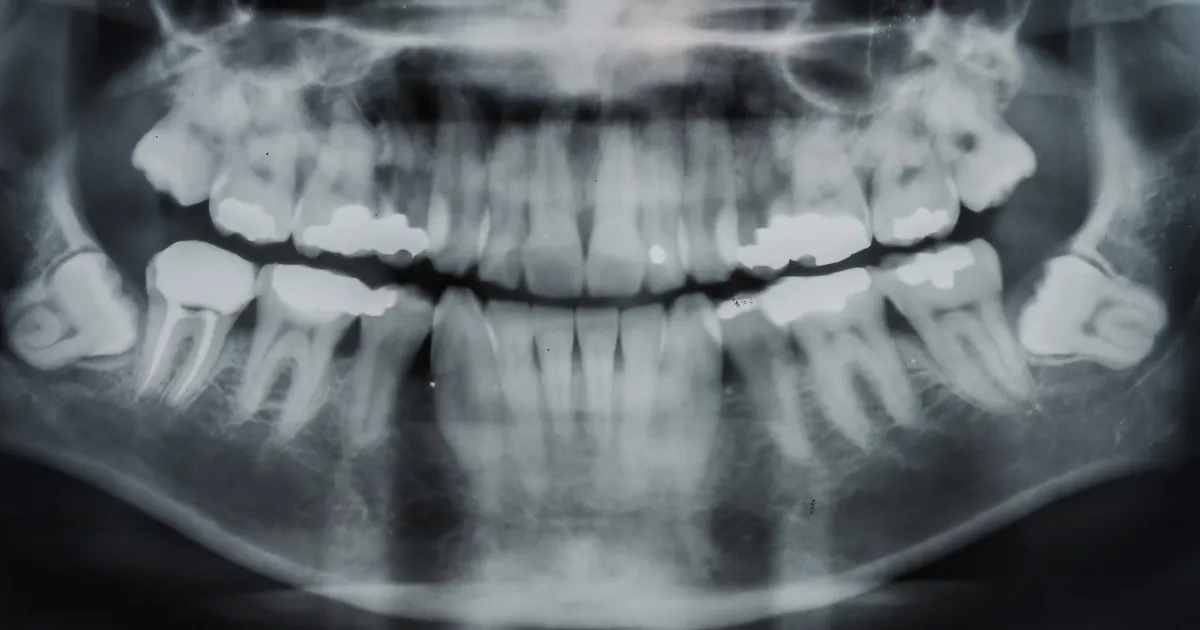

まず、抜歯前には口腔内の検査が必要です。口腔内の状態を評価するために、レントゲン撮影やCTスキャンが行われることがあります。これにより、歯の位置や形状、周囲の骨の状態などを詳しく把握し、手術の計画を立てることができます。

まず、口腔内のレントゲン撮影が必要です。これによって、親知らずの位置や形態、周囲の歯や骨の状態を把握します。また、歯科医師が術前に行う口腔内の検査も重要です。歯周病や歯垢、歯石がある場合は、手術前に治療が必要です。

レントゲン画像では基本的に硬組織が白く見えるのですが、顎の骨が親知らずによって溶けていて黒く抜けて見えたりすると原因となっているかもしれませんね。